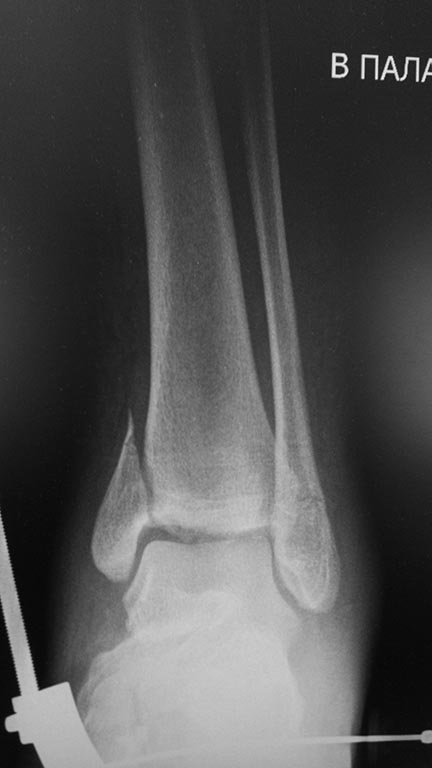

Мне кажется, что вопрос, поставленный Вами: "Возможно ли одномоментно устранить подвывих или только на аппарате Иллизарова?", отражает не совсем ясное понимание ситуации. Что значит устранить подвывих? А пластику ложных суставов внутренней лодыжки и заднего края большеберцовой кости не нужно делать? И ось голеностопного сустава нужно исправлять. То есть делать остеотомию наружной лодыжки (если она срослась, по снимку не очень понял). Артродез голеностопного сустава в такой ситуации очень сложен. Если же добиться сращения всех переломов в правильном положении, артродез вполне можно отсрочить на несколько лет, что для молодого пациента достаточно важно. Но в конечном счете все определяется Вашим умением и ясным представлением того, чего Вы хотите добиться своей операцией. Во вложении - в чем-то похожий случай. Оперировал эту пациентку 23 лет 11 лет назад через 8 месяцев после похожего на представленный Вами остеосинтез. На первой операции перелом малоберцовой кости в нижней трети был просто не замечен. За счет восстановления оси быстро развившийся артроз протекал благоприятно. В результате артродез был выполнен только в прошлом году, через 10 лет после второй операции. И боли беспокоили пациентку только в течение года перед артродезом.